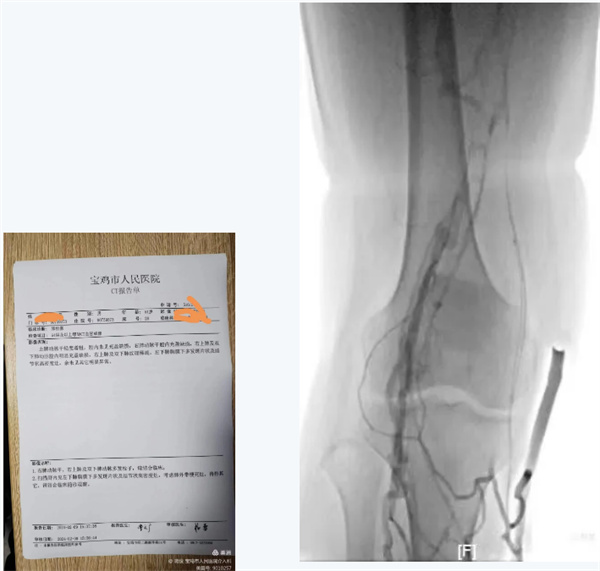

肺動脈CTA提示肺動脈血栓栓塞癥

下肢靜脈DSA造影提示大量新鮮血栓